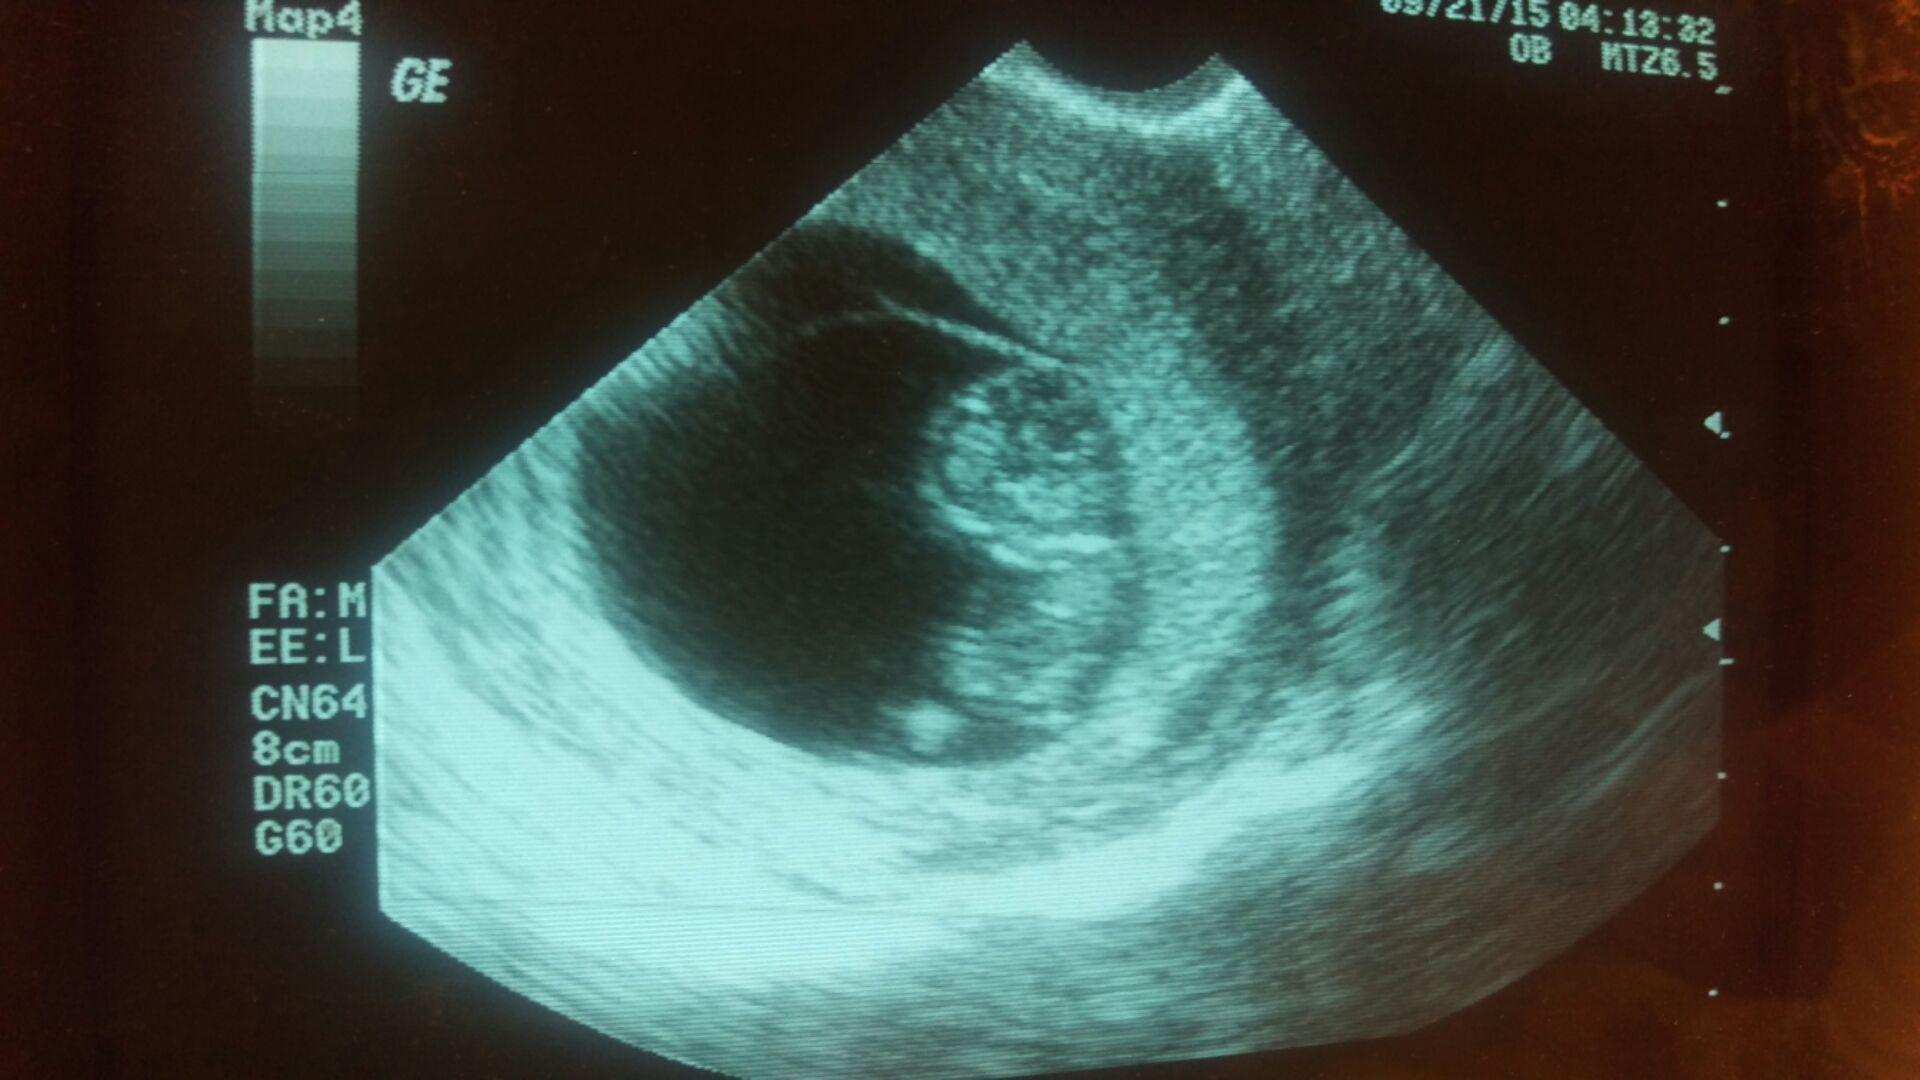

hey beautiful ladies how many of you have had your first ultrasound? How was your experience? I couldnt hold my tears when i saw the tiny being inside me with its heart beating. Such a wonderful thing to experience really:) my husband just couldnt hold smiling and looking away from the baby. Absolutely loved the experience. Here is the pic of the first ultrasound. The baby is 8 weeks 5 days as of today. Please share your experience. Would love to know